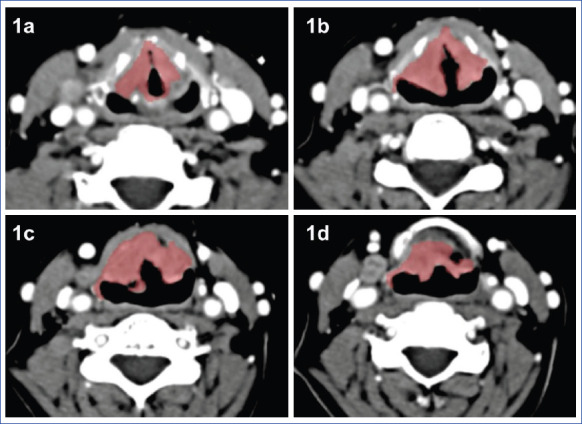

研究目的在这项回顾性研究中,我们评估了肿瘤体积、分级侵犯深度在预测颈淋巴结转移中的有效性:方法: 对接受手术的177例喉鳞癌患者进行回顾性评估。分析了患者的年龄、性别、肿瘤-结节-转移(TNM)分期、分级、浸润深度和计算机断层扫描(CT)肿瘤体积。结果:32名患者(29.91%)的宫颈淋巴结呈阳性。13例(46.43%)分化较差的肿瘤和19例(24.05%)分化中等的肿瘤发现了淋巴结转移。淋巴结阴性患者的平均体积为(2.15±0.14)毫升,淋巴结阳性患者的平均体积为(2.97±1.05)毫升。淋巴结阴性患者的平均浸润深度为(10.1±0.87)毫米,淋巴结阳性患者的平均浸润深度为(11.3±1.05)毫米。肿瘤分级和体积可成功预测喉鳞状细胞癌患者的淋巴结转移,但浸润深度与淋巴结转移无关(分别为P=0.047、P=0.0022、P=0.916):结论:肿瘤分级和体积可预测喉鳞状细胞癌患者的颈淋巴结转移,而浸润深度则无法预测。通过放射学方法计算肿瘤体积有助于预测淋巴结转移,从而最大限度地减少浸润深度等测量数据的可变性。

Results: Thirty two patients (29.91%) had positive cervical lymph nodes. Lymph node metastasis is detected in 13 (46.43%) poorly differentiated tumors, and in 19 (24.05%) moderate-well differentiated tumors. Mean volume was 2.15±0.14 cc in lymph node negative patients and 2.97±1.05 cc in lymph node positive patients. Mean invasion depth was 10.1±0.87 mm in lymph node negative patients and in 11.3±1.05 mm lymph node positive patients. The tumor grade and volume predicted successfully lymph node metastasis in patients with squamous cell carcinoma of the larynx, however invasion depth was not associated with nodal metastasis (p=0.047, p=0.0022, p=0.916, respectively).

Conclusion: The tumor grade and volume could predict cervical lymph node metastasis in patients with squamous cell carcinoma of the larynx, whereas the depth of invasion did not. Calculation of the tumor volume radiologically can help predict lymph node metastasis by minimizing the variability in measurements such as the depth of invasion.